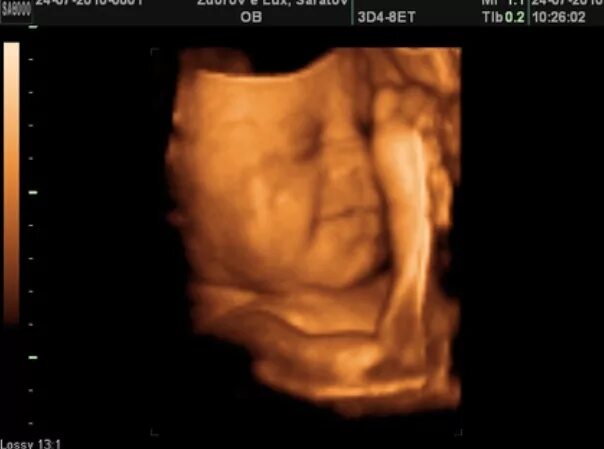

Плод 33